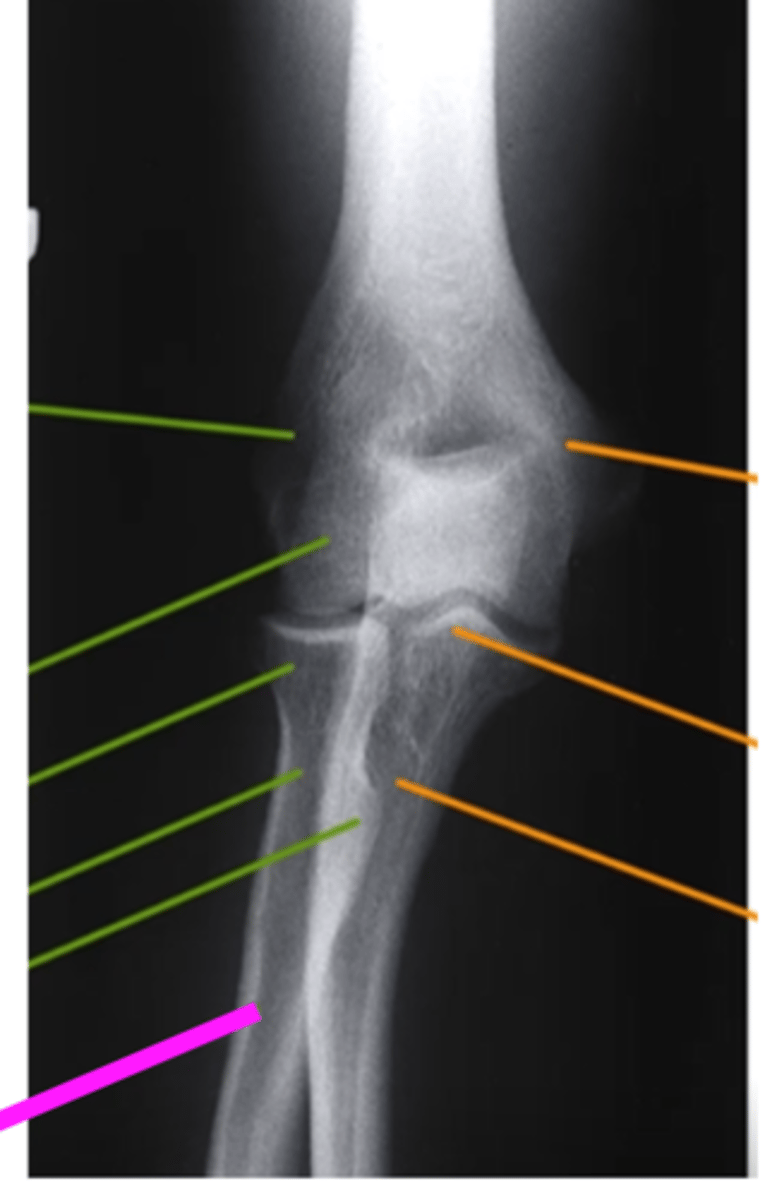

AP Elbow

what view is this

lateral epicondyle

what does the pink line point to?

medial epicondyle

Capitulum

coronoid process

shaft of ulna

shaft of the radius

radial tuberosity

radial head

radial neck